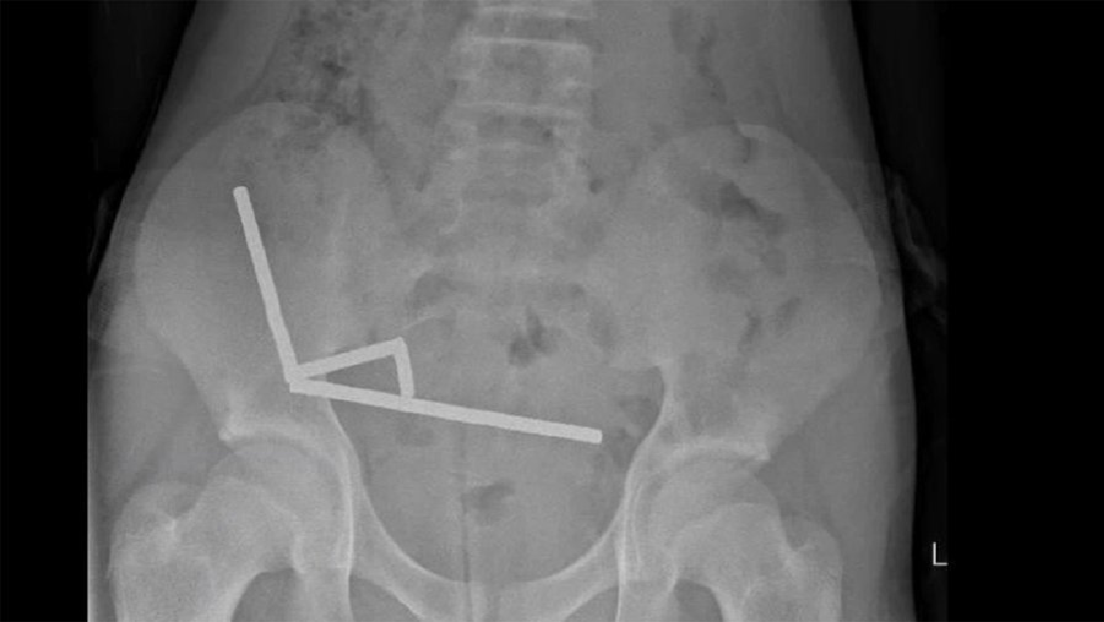

Adolescente pierde parte del intestino tras ingerir unos 100 imanes